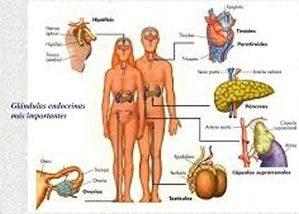

Además, en el colon se localizan terminales nerviosas o puntos reflejos, que inciden en otros sistemas:

- En el sistema endocrino que secreta hormonas, desde distintas glándulas, para que actúen en células específicas que propiciarán un efecto deseado en el organismo.

Los complejos mecanismos por los que actúan estos y otros sistemas, como el digestivo, el respiratorio y el inmunológico, permiten que un cuerpo conserve su estado de salud, gracias al trabajo en equipo ejercido por la unidad funcional básica de nuestro cuerpo: la célula.

Si bien su tamaño es pequeño, su cantidad es numerosa, son 100 millones de engranes trabajando en conjunto, para que los distintos sistemas que componen a esta máquina, lo hagan armoniosamente y cabalmente se cumpla su carácter de Perfecta.